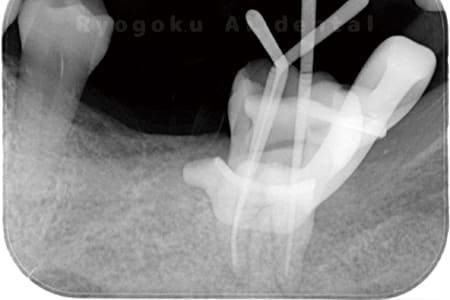

Case01

根管内の異物

- 原因

- 根管内異物(ファイル破折)による慢性根尖性歯周炎

- 治療期間

- 3ヶ月

- 治療内容

- マイクロスコープを使用した根管内異物除去並びにマイクロエンド

- 治療費用

- 121,000円(ファイル除去費用も込み)

他院で細い器具(ファイル)が根管内に破折した状態で、咬合痛を主訴に来院された患者様です。ファイルをマイクロスコープ下で除去し、根管治療を行ないました。

<リスク・副作用>

術後は痛み、腫れ、痺れなどの副作用が生じる場合があります。症状が再発する可能性があります。